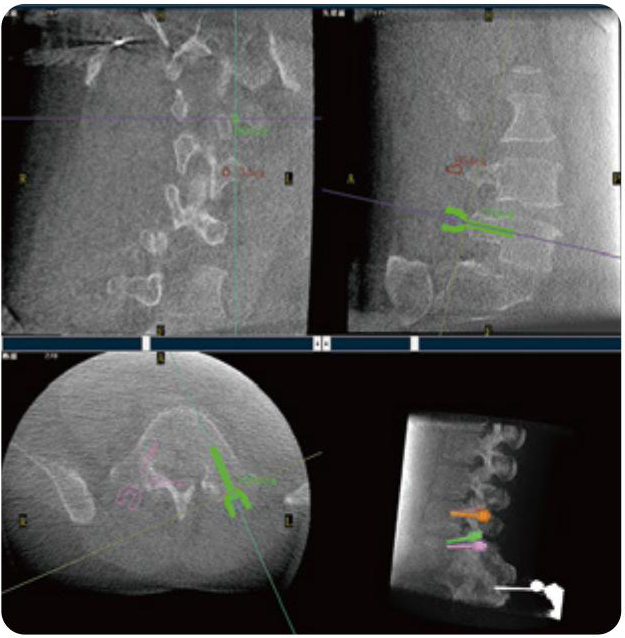

PL300B可应用于多节段脊柱外科手术,辅助医生定位病灶部位,为脊柱外科手术(经皮椎体成形术、椎弓根螺钉内固定术等术式)提供术前手术流程规划、入钉位置、角度可视化引导,模拟仿真入钉辅助。

PL300B搭配糖心vlog 自主研发生产的平板3D C形臂,借助一体化自适应配准( 轨迹配准)技术,通过追踪C形臂三维采集轨迹,自动完成图像坐标建立和系统坐标配准。配准精度更高,操作步骤少,系统运作效率高。